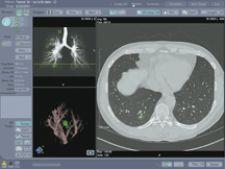

With R2’s Version 2.1 ImageChecker CT Lung CAD System, results from the AutoPoint Temporal Comparison tool (for tracking lung nodule growth between current and prior multislice CT exams) can now be sent to a PACS workstation for full enterprise accessibility, without the need for R2’s dedicated CT CAD workstation. According to the manufacturer, with the new Version 2.1 software, R2’s Pulmonary Artery Patency Exam (PE) tool features a new algorithm to aid physicians in more effectively detecting intravascular filling defects, such as pulmonary embolism, during review of multislice CT exams.